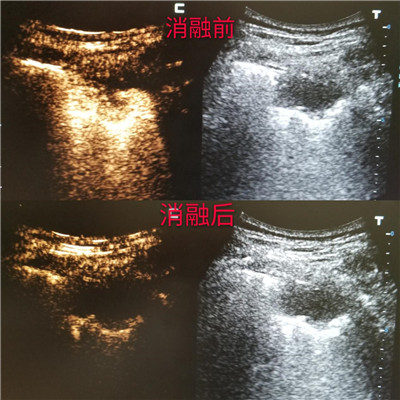

超声造影评估微波消融治疗情况

超声造影作为目前最先进的超声成像技术,能够提供比普通超声及彩色多普勒超声更丰富、更明确的诊断信息。它在常规超声检查的基础上,通过静脉注射超声造影剂,来增强人体的血流信号,实时动态地观察正常脏器和肿块的血流灌注情况,提高超声诊断的特异性和敏感性。微波肿瘤消融术是的肿瘤微创治疗技术,它的原理使局部肿瘤组织凝固性坏死,最终形成液化灶或纤维化,起到原位灭活肿瘤组织的作用。具有疗效好、创伤小、痛苦小、恢复快、适应症广等优点。大多肺癌微波消融术是在CT引导下进行,但是对于紧贴胸壁的周围型肺癌,超声可以实时清晰显示。而超声造影在微波消融治疗前、中、后应用,可降低穿刺并发症的风险,确定治疗术中监测评价疗效。